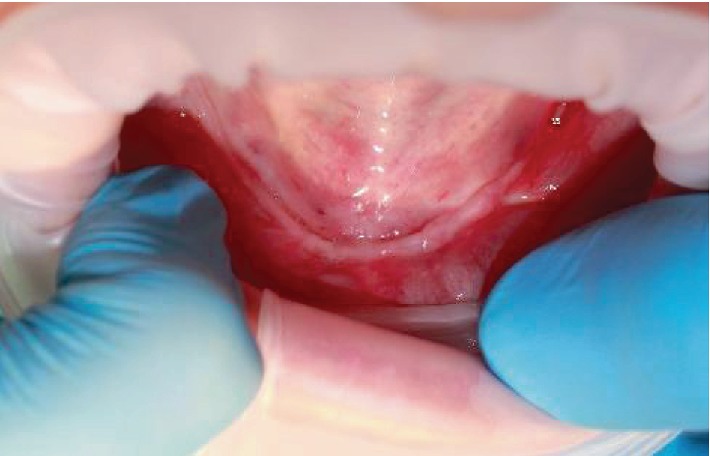

При клиническом осмотре было выявлено отсутствие чёткой границы между преддверием рта и полостью рта. Также была зафиксирована выраженная атрофия альвеолярного гребня нижней челюсти.

Осмотр полости рта. Выраженная атрофия альвеолярного отростка нижней челюсти.